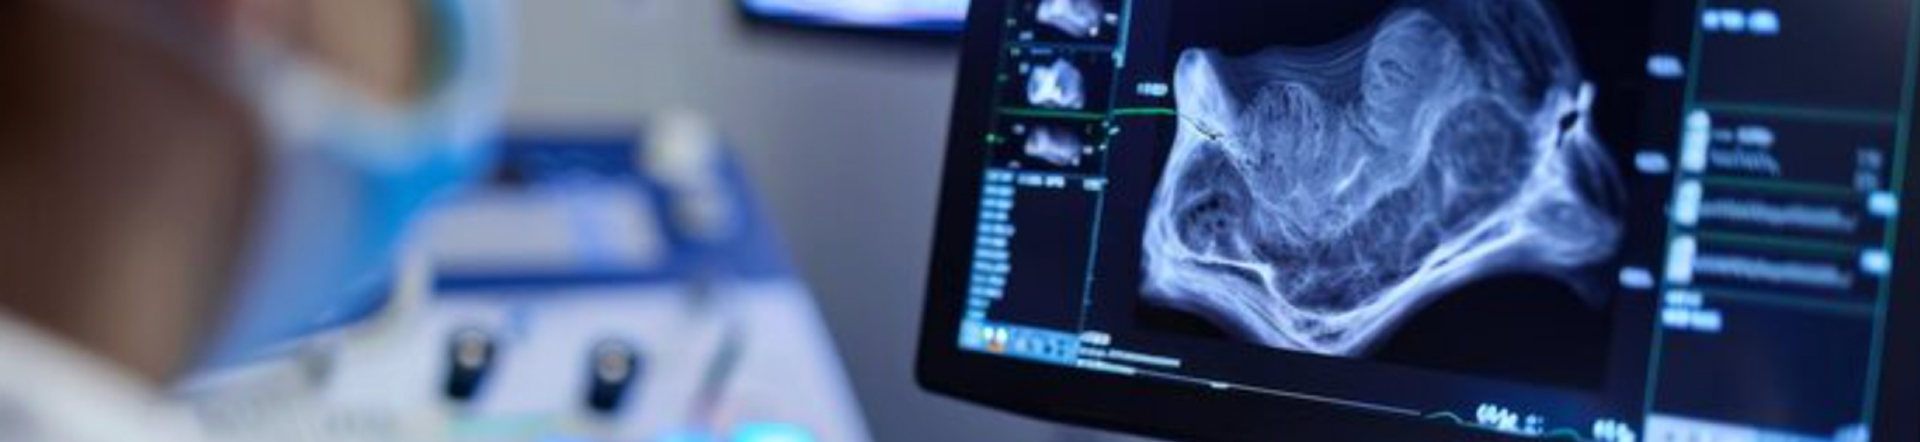

- Ecografia organelor interne (abdomen, pelvis, rinichi, ficat, pancreas, vezică urinară etc.)

- Ecografie obstetricală:

- Primul trimestru de sarcină

- Trimestrul II și III de sarcină